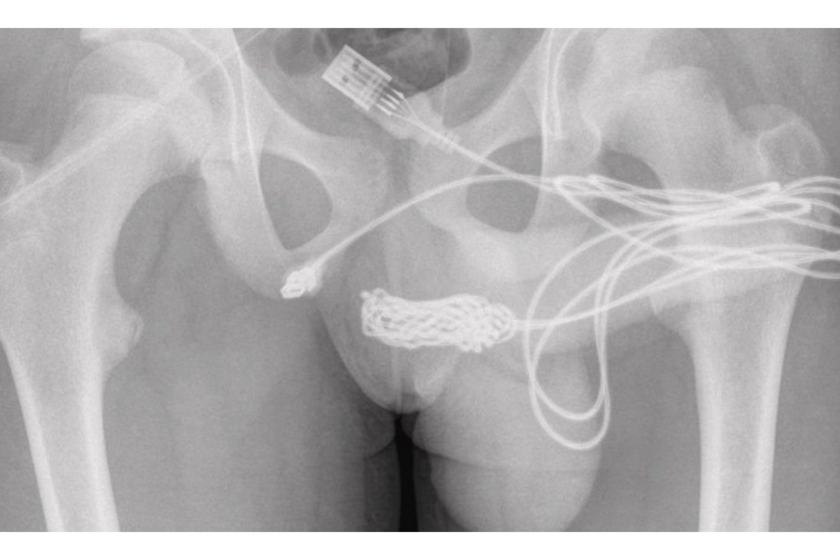

Raio-x de partes íntimas. Créditos: Divulgação/Urulogy Case Reports

Todos os anos, milhares de pessoas dão entrada em emergências nos Estados Unidos por um motivo tão inusitado quanto delicado: objetos presos em partes íntimas do corpo. Os dados fazem parte do Sistema Nacional Eletrônico de Vigilância de Lesões (NEISS), mantido pela Comissão de Segurança de Produtos de Consumo dos EUA, que registra atendimentos médicos e suas causas. A lista mostrou uma variedade  de itens removidos dos órgãos sexuais masculino e feminino, além de objetos incomuns removidos do reto de pessoas.

Entre os atendimentos envolvendo o órgão sexual masculino, os registros mostram uma combinação de itens comuns e escolhas difíceis de explicar. Aparecem na lista baterias, canetas, lápis, pentes, clipes de papel e grampos, objetos pequenos, rígidos e facilmente acessíveis

Mas há também casos mais inesperados, como peças de xadrez, cordas de guitarra, chaves Allen, ímãs, parafusos, termômetros, vidro e até caules e miolo da maçã. Em muitos desses episódios, médicos relatam que o problema se agrava porque a pessoa tenta resolver sozinha antes de procurar ajuda, recorrendo a ferramentas improvisadas que só pioram a situação.